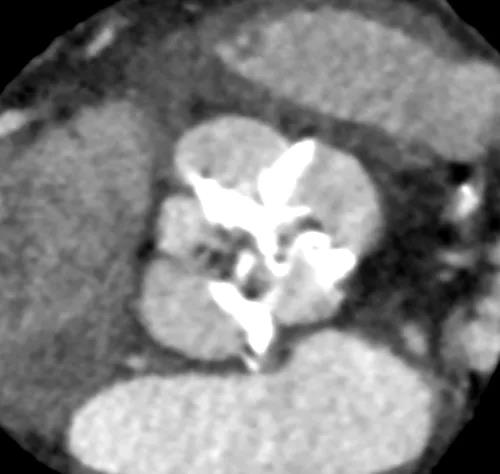

病例3(经颈动脉TAVI)

患者男性,67岁,头晕伴胸闷、胸痛6月余,术前心脏超声提示主动脉瓣增厚钙化伴重度狭窄,峰值流速4.9m/s,峰值压差94mmHg,平均跨瓣压差59mmHg,瓣口面积0.6cm2。CT显示主动脉瓣为Type I型二叶瓣,瓣叶边缘及左右冠瓣融合嵴严重钙化,致瓣口极度细窄。瓣环面积528.8mm2,测算直径25.9mm,左冠脉开口高度14.4mm,右冠脉开口高度17.5mm。患者合并重度肺气肿、多发肺大泡、支气管扩张,肺功能极差,静息状态下氧饱和度仅约80%,STS评分8.6%,属于外科手术高风险患者。

主动脉瓣瓣环 Type I型二叶瓣

瓣叶及左右冠瓣融合嵴重度钙化 重度肺气肿、多发肺大泡